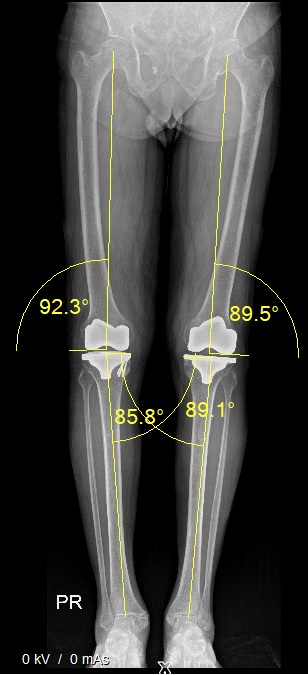

Recently, knee alignment has been found to fall into one of 9 categories and each patient who undergoes a knee replacement would fall in one of these 9 categories. The aim of conventional TKA was to get a perfect 180-degree alignment on standing view which would correspond to CPAK category V. In spite of good alignment, a section of patients arestill unhappy, and the hypothesis was that the change of CPAK category leads to dissatisfaction.

Pre Surgical Standing Knee X Ray Both Knee CPAC Type 1